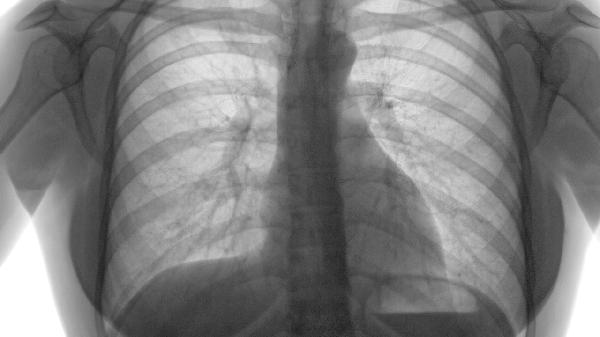

肺气肿症状主要表现为早期活动后气短、进展期持续性呼吸困难、终末期呼吸衰竭伴并发症。 1、早期表现: 轻度活动后气...

肺气肿常见症状包括气短、慢性咳嗽、胸闷、乏力等,病情发展可能出现桶状胸、体重下降等体征。 1、气短 早期表现为活...